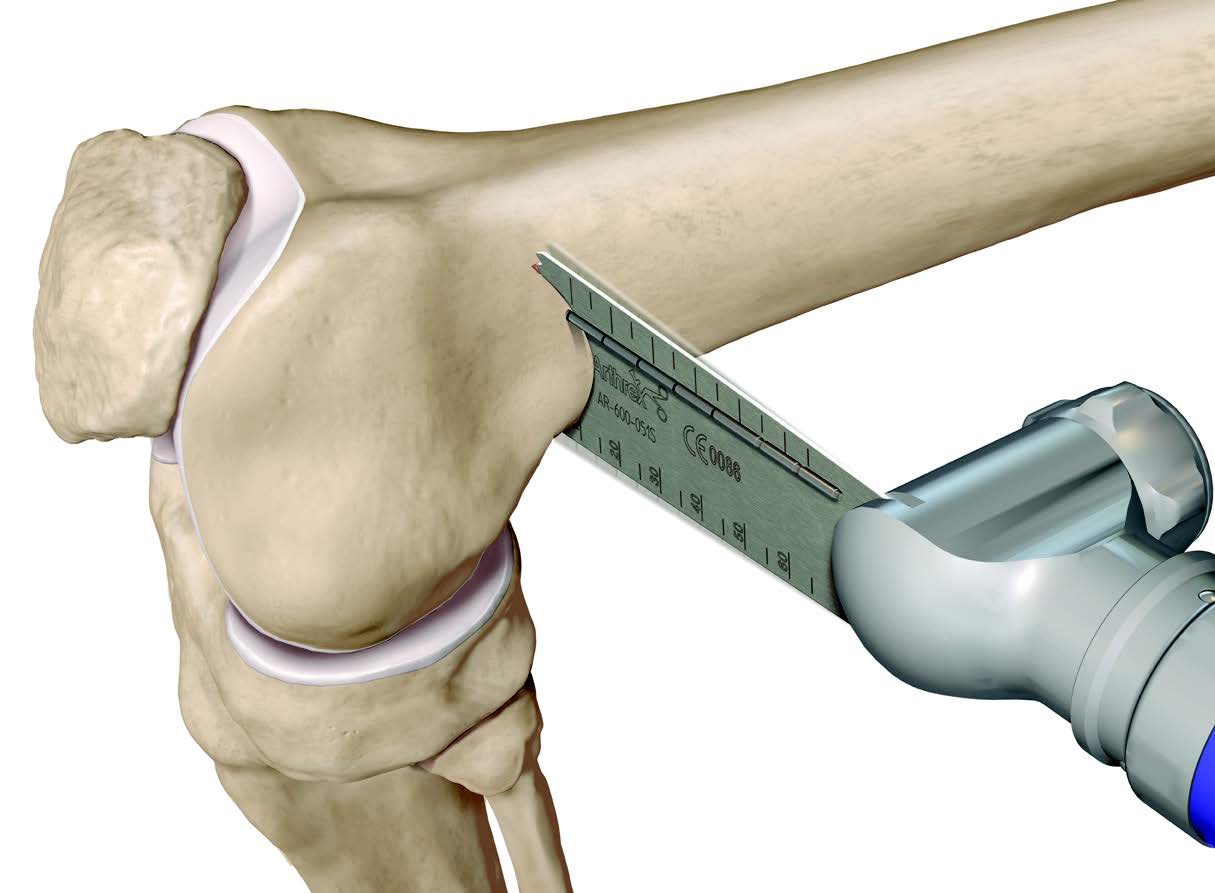

Osteotomy

- insert guide wires

- proximal lateral to distal medial

- proximal 1 - 2 cm above flare of lateral condyle

- aim towards adductor tubercle

- risk of medial hinge fracture reduced if osteotomy at or distal to adductor tubercle

- ensure these are perpendicular to the femoral shaft in the sagittal plane

- above patellofemoral joint and posterior condyles

- stop osteotomy 1 cm short of medial cortex